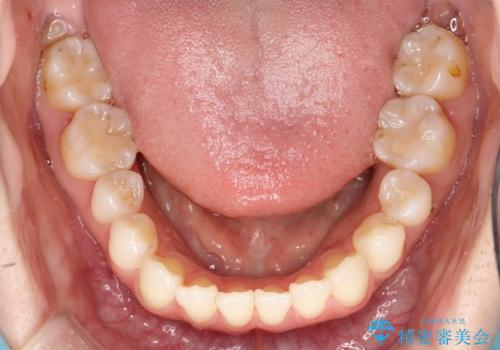

軽度の前歯のガタガタをインビザラインでの目立たない矯正

- 前歯のガタガタを主訴に来院されました。

軽度であったため、枚数制限のあるタイプのインビザラインのプランで治療することとしました。